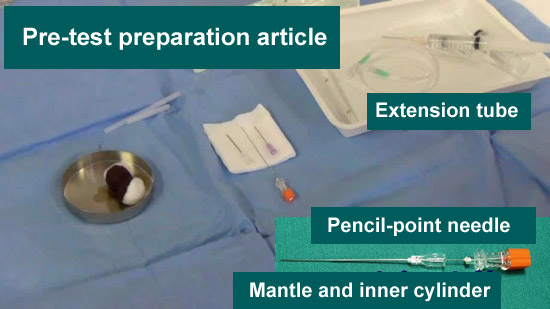

Preparations for RI examination

●Puncture needle

25-gauge pencil-point needle (Puncture needle)

22-gauge needle (Guide needle)

●Extension tube

●Local anesthesia

24-gauge needle (Local anesthesia needle)

●Contrast medium

Omnipaque for computed tomography (CT) 10 mL

Indium 1 mL